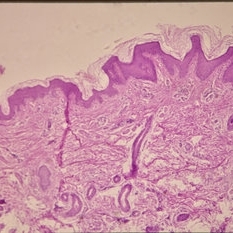

Histopathology of Linear Sebaceous Nevus Syndrome

Histopathology of Linear Sebaceous Nevus Syndrome

Feb 20 2015 by H. Michael Lambert, MD

Histopathology of linear sebaceous nevus syndrome.

Condition/keywords: histopathology, linear nevus sebaceous syndrome